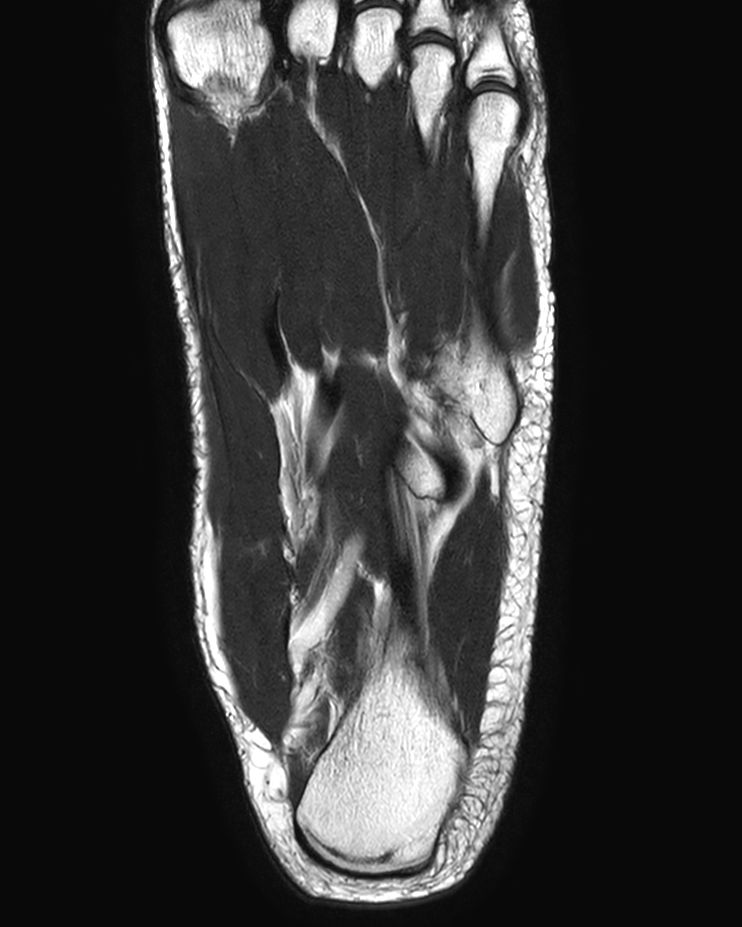

Foot with plantar fascitis

Coronal T2w TSECompressed SENSE